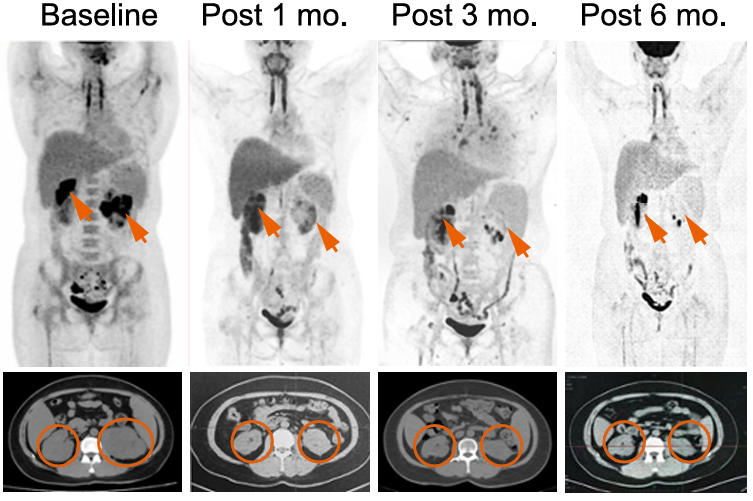

研究团队先后开展了两项IIT临床试验。第一项试验采用TCR与SPPL3双敲除策略,结果显示在安全性方面未出现 GvHD,但 CAR-T 在体内的持续时间有限,通过对输入产品中残存CD3+ CAR-T的扩增动力学分析,研究者推测SPPL3敲除所形成的“糖苷盾”能够避免GvHD,而保留TCR基底信号则可能对维持T细胞长期存活至关重要。基于这一假设,团队进一步开展了仅敲除SPPL3、保留TCR的第二项临床试验。结果显示,患者体内的CAR-T可持续存在6个月以上,未观察到典型GvHD或严重免疫并发症,部分患者获得持久缓解。

Figure 3. Long persistence of SPPL3KO/anti-CD19 CAR-T cells in vivo

这一结果首次证明:SPPL3缺失诱导的糖基化重塑能够突破异体CAR-T的免疫屏障,而内源性TCR信号对细胞持久性具有不可替代的作用。该发现为通用型CAR-T的设计与开发提供了全新的策略范式。